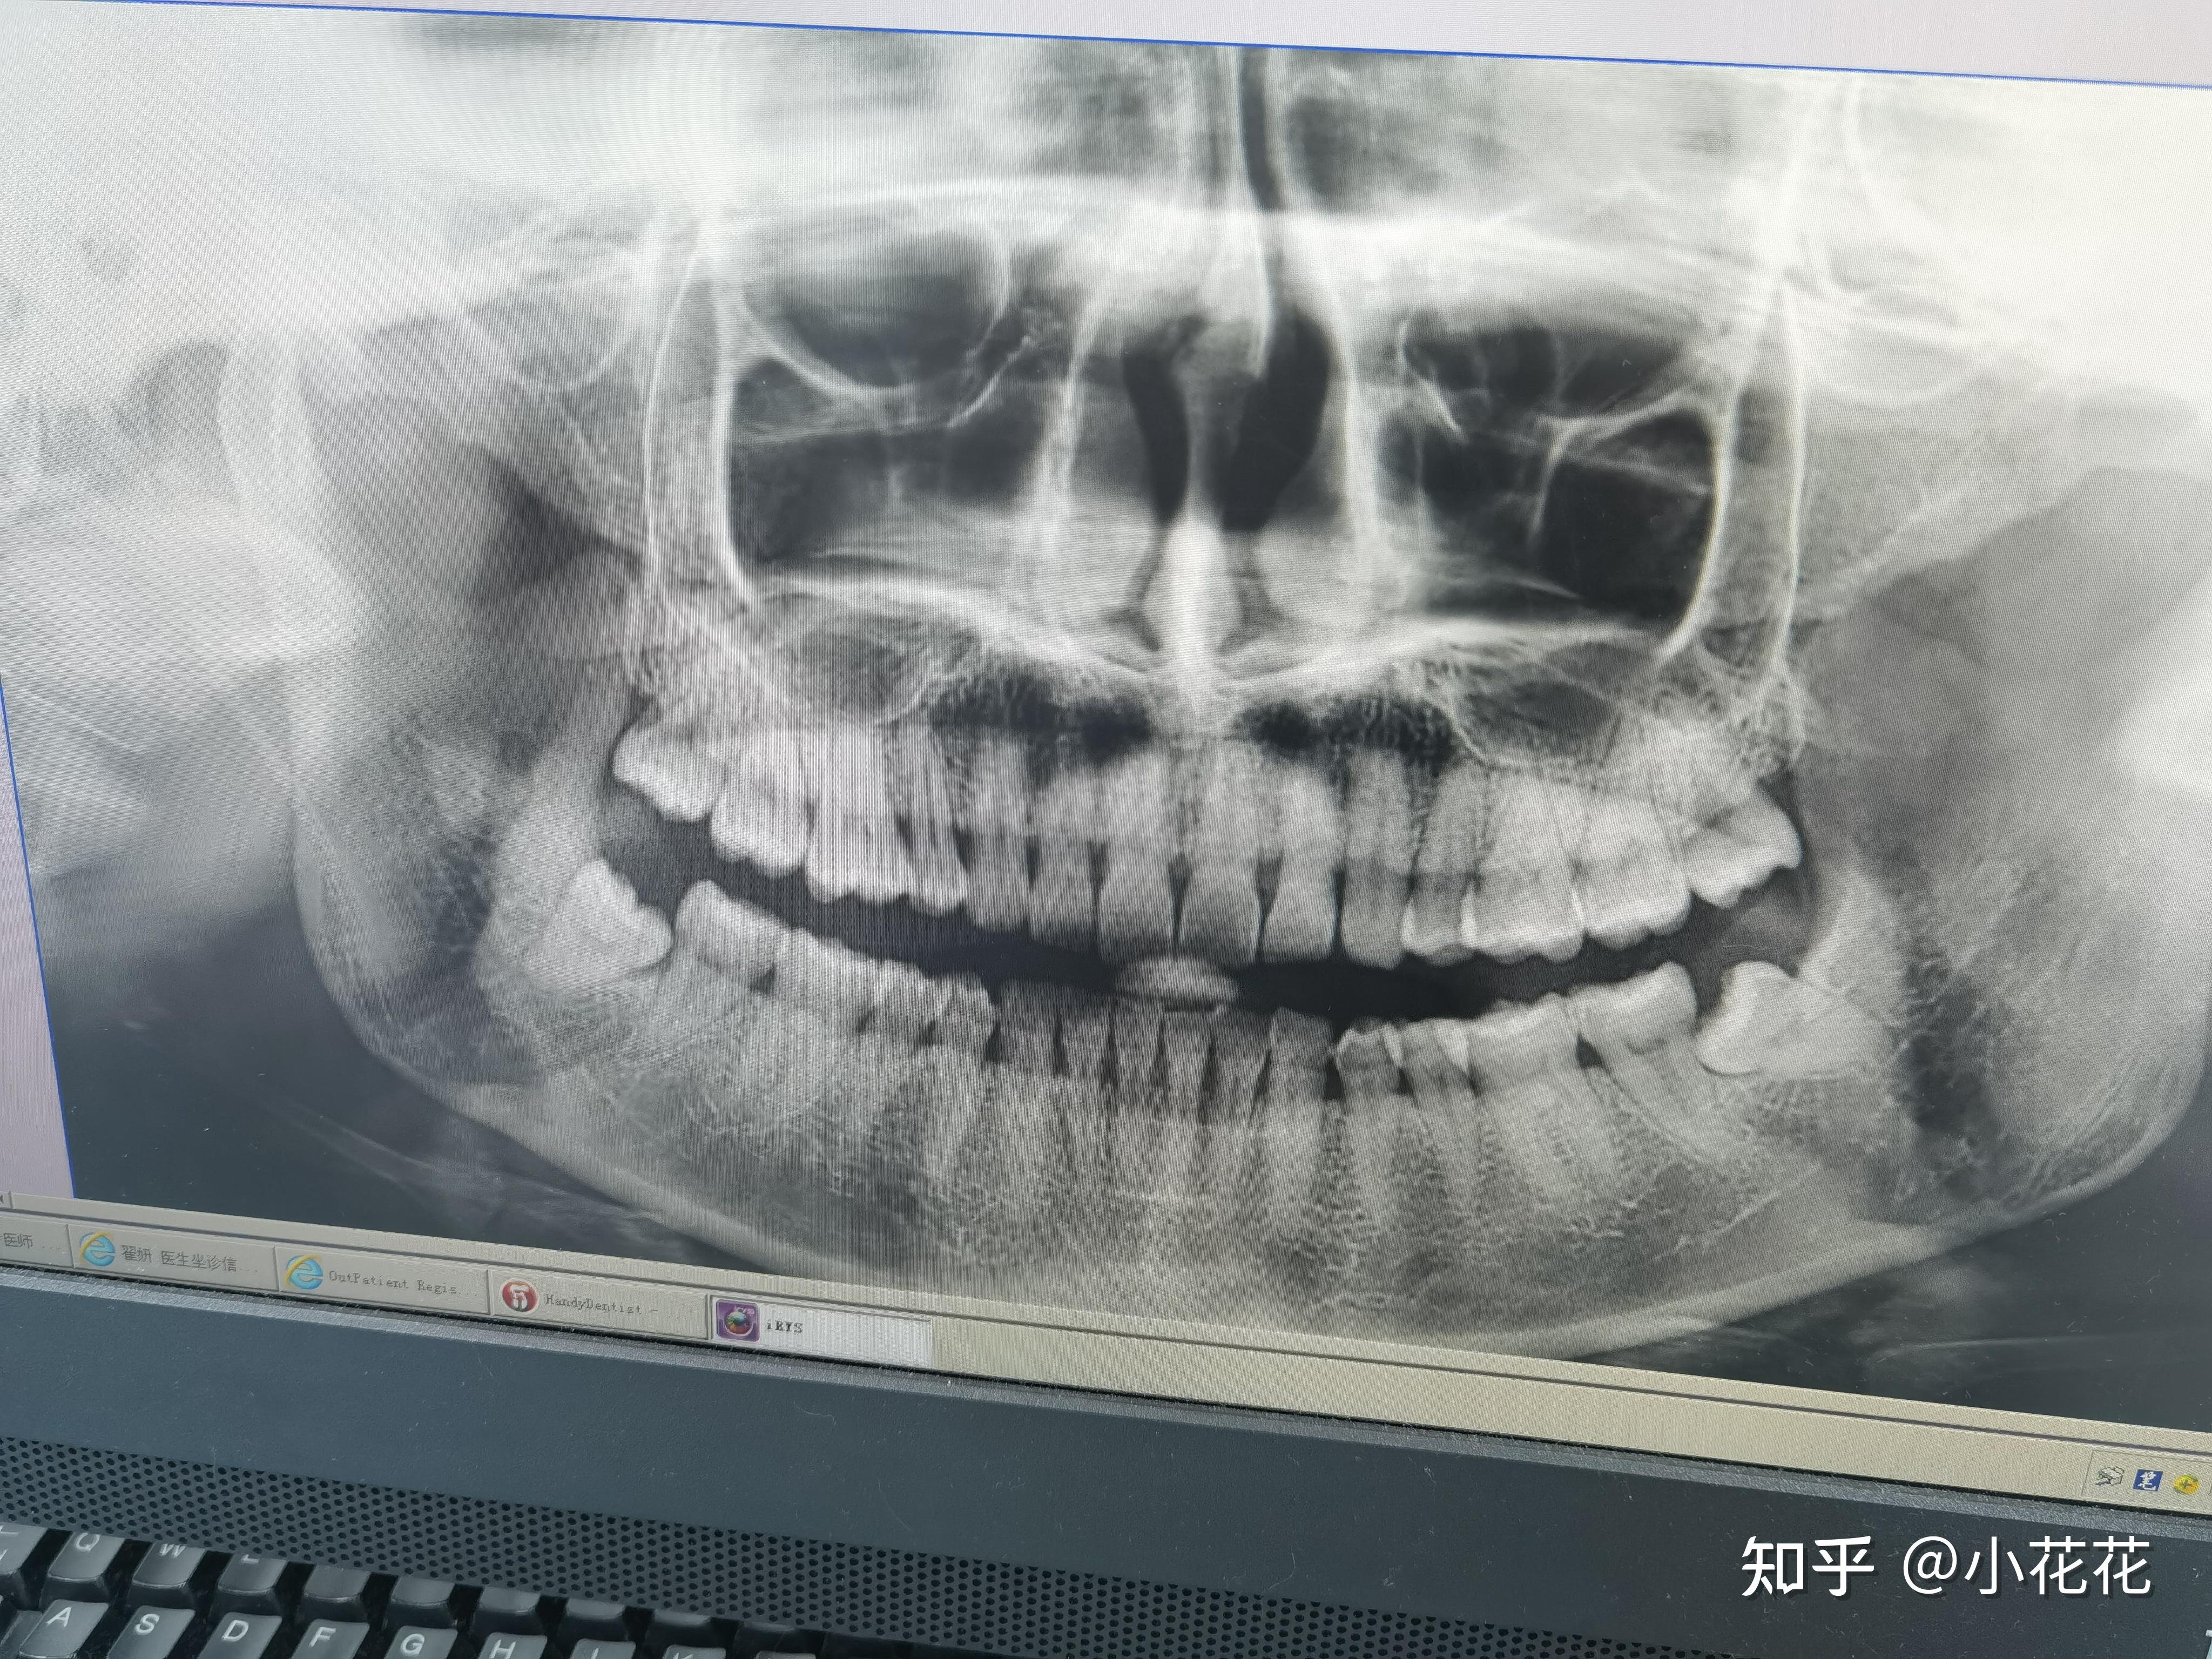

我的急性冠周炎(智齿发炎)以及拔四颗智齿的经历

图片尺寸4096x3072